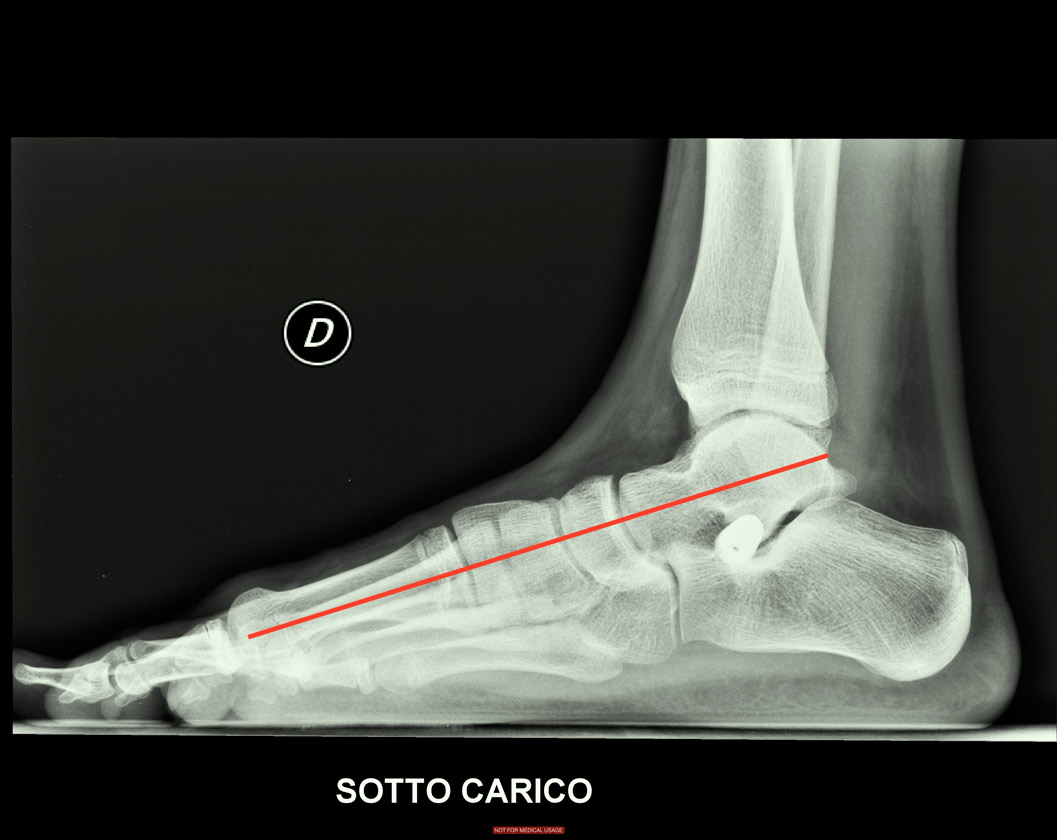

piede piatto di bambino

Con un intervento mini invasivo si può oggi correggere anche un piede gravemente piatto: è consigliabile intervenire ad accrescimento non ultimato (l’ideale è intorno ai 9-10 anni), anche se nel caso presentato il paziente, pur avendo eseguito la prima radiografia a 12 anni, ha ritardato l’intervento di 2 anni.

Fig. 2 Radiografia postoperatoria: è stata inserita una vite troncoconica all’interno del seno del tarso che ha “alzato” l’astragalo e ha ripristinato un corretto allineamento delle ossa tarsali (linea rossa). L’intervento ha una durata di 10 min circa con una cicatrice di 1,5 cm che con gli anni diventerà pressoché invisibile.